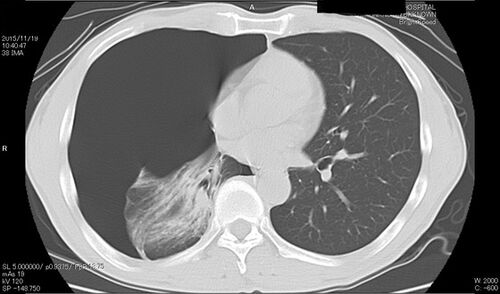

気胸体験と “Kha” の恐怖

本投稿はYahooブログ「脳と心とブッダの覚り」2015/12/23「気胸体験と“Kha”の恐怖」を元としているが、これもまたどのように移転しようかあるいはしないか、で悩んでしまった記事だ。 しかし、ここに書かれた「恐怖の気胸体験」は私にとって色々な意味で忘れ…